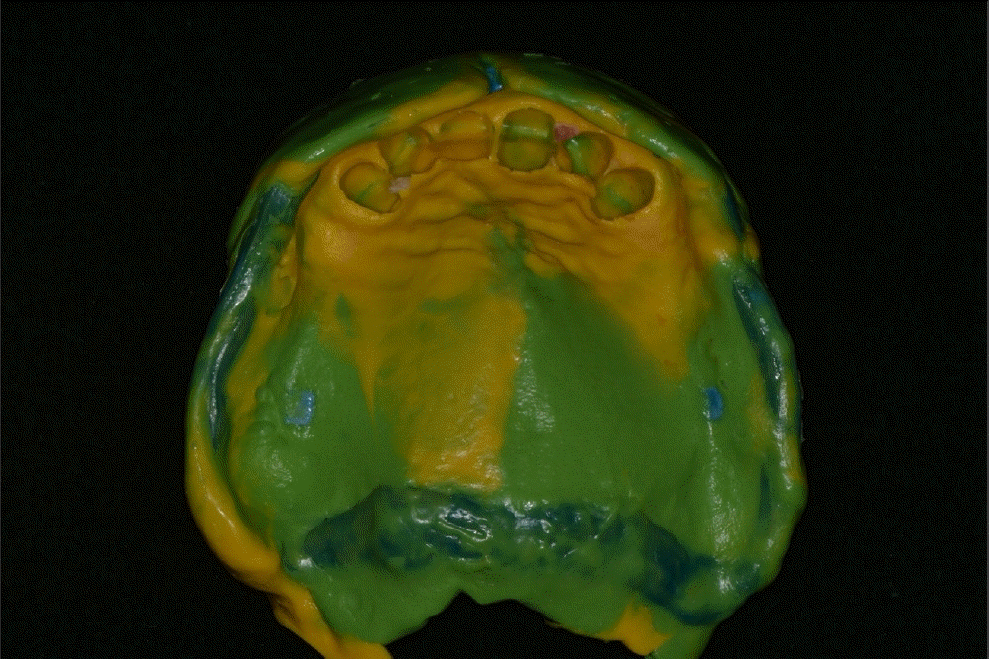

본 증례의 환자는 76세의 여성으로 상악 6전치만 잔존한 상태로 상악 가철성 국소의치의 제작을 위해 내원하였다. 상악은 6전치 중 상악 우측 견치와 좌측 견치의 상태는 동요도 및 파절 상태 없이 양호하였고, 상악 우측 측절치는 총생 상태였으며, 상악 우측 중절치와 상악 좌측 측절치를 이용해 3본 고정성 가공의치 형태로 상악 좌측 중절치의 수복이 되어 있는 상태였고, 상악 잔존 치조제의 상태는 중등도의 흡수 상태가 관찰되었다. 하악은 하악 좌측 제 2소구치는 잔존 치근 상태였다(Fig. 1). 상악의 경우엔 임시의치를 사용중이었고, 잔존 치근 상태인 하악 좌측 제 2소구치는 발거를 진행하였다. 전신병력으로는 B형 간염, 신장 투석, 파킨슨, 당뇨, 고혈압 및 협심증으로 다양한 약을 복용중이었고 비용 및 전신병력의 이유로 임플란트와 같은 수술적인 치료방법의 치료는 어려운 상태였다.상악은 양측 구치부의 결손이 있는 Kennedy Class I 으로 분류하고, 후방 결손부의 수복을 위해서 상악 가철성 국소의치의 제작을 진행하기로 결정하였다. 상악 가철성 국소의치의 디자인은 양측 상악 견치에 후방연장 국소의치의 유지를 위해 설면 레스트와 원심 유도면, 조직 언더컷으로 인해 RPA 클라스프를 설계하였고, 잔존 치아의 개수가 적어 주연결장치는 구개부를 대부분 피개하는 구개판형 연결장치를 설계하였다. 간접 유지의 역할을 위해 추가적인 설면 레스트의 부여를 고려하였으나 양측 측절치에 설면 레스트의 형성은 상악 우측 측절치의 총생 및 상악 좌측 측절치의 기존 보철 수복물로 인해 한계가 있었다(Fig. 2). 의치의 무게로 인한 탈락을 최대한 보완해보고자 금속 구조물의 제작을 코발트-크롬 합금보다는 보다 가벼운 특징을 가진 티타늄 합금(Ti-6Al-4V)을 이용하여 제작하기로 결정하였고, 7년 이내 요양급여를 통한 보험의치 적용을 받은 기록이 있어 비보험 진료로 진행하기로 하였다.해당 수복의 진행을 위해 양측 견치에 설면 레스트 시트를 구강 내 직접 형성 하였고 삽입 철거로를 고려하여 원심면의 치질 성형을 시행하였다(Fig. 2). 이후 개인 트레이를 제작 후 부가중합형 실리콘(Selection-K V.P.S, Shinhung Co., Seoul, Korea)를 이용해 기능인상채득을 시행하였다(Fig. 3). 이후 주모형을 제작하였고 제작된 주모형을 모델 스캐너(DOF Freedom HD, DOF Inc., Seoul, Korea)를 이용해 스캔하여 디지털 데이터를 형성하였다(Fig. 4). 이후 디지털 데이터를 이용하여 CAD 프로그램(3Shape dental system, 3Shape Inc., Copenhagen, Denmark)를 이용하여 금속 구조물을 디자인하였다(Fig. 5). 이후 해당 디자인된 금속 구조물을 선택적 레이저 용융 방식(SLM)의 3D 프린터(David 1.0, Merain Co., Incheon, Korea)를 이용하여 티타늄 합금(Ti-6Al-4V)으로 금속 구조물을 제작하였다. 또한 티타늄 합금과의 무게 비교를 코발트-크롬 재질의 금속 구조물도 티타늄 합금(Ti-6Al-4V)의 금속 구조물 제작에 사용한 동일한 CAD 파일을 이용하여 3D 프린팅을 통해 제작하였다.제작한 티타늄 합금(Ti-6Al-4V)과 코발트-크롬 합금의 금속 구조물의 후처리를 완료 후 주모형에 적합도 확인 및 무게 측정을 시행하였으며, 티타늄 합금(Ti-6Al-4V) 금속 구조물의 무게는 5.6g 이었고, 코발트-크롬 합금의 무게는 9.5g으로 티타늄 합금(Ti-6Al-4V)의 무게가 코발트-크롬 합금보다 41% 정도 더 가벼운 무게를 나타냈다(Fig. 6).제작된 티타늄 합금(Ti-6Al-4V) 금속 구조물의 적합을 환자 구강내에서 확인하였고, 이후 기록상을 제작하여 악간관계 기록을 채득 후 교합기에 부착하여 치아배열을 시행하였으며, 균일하게 중심교합 시 균일한 교합접촉을 이루는지 확인하였다(Fig. 7).